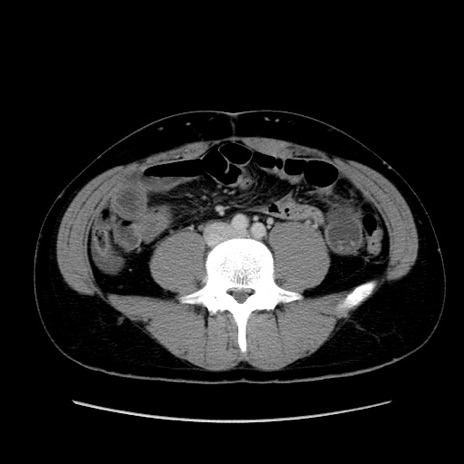

症例36(横断像)

【症例】20歳代 男性

【主訴】心窩部痛

【現病歴】今朝より上腹部痛あり。一旦軽快していたが再度出現したため救急要請。昨日夕に白身の魚を含む刺身を食べた。

【身体所見】BP 136/89mmHg、HR 74/min、BT 37.0℃、腹部:膨満、軟、心窩部に圧痛あり。反跳痛なし、筋性防御なし、腸雑音やや亢進あり。

【データ】WBC 17700、CRP 0.48